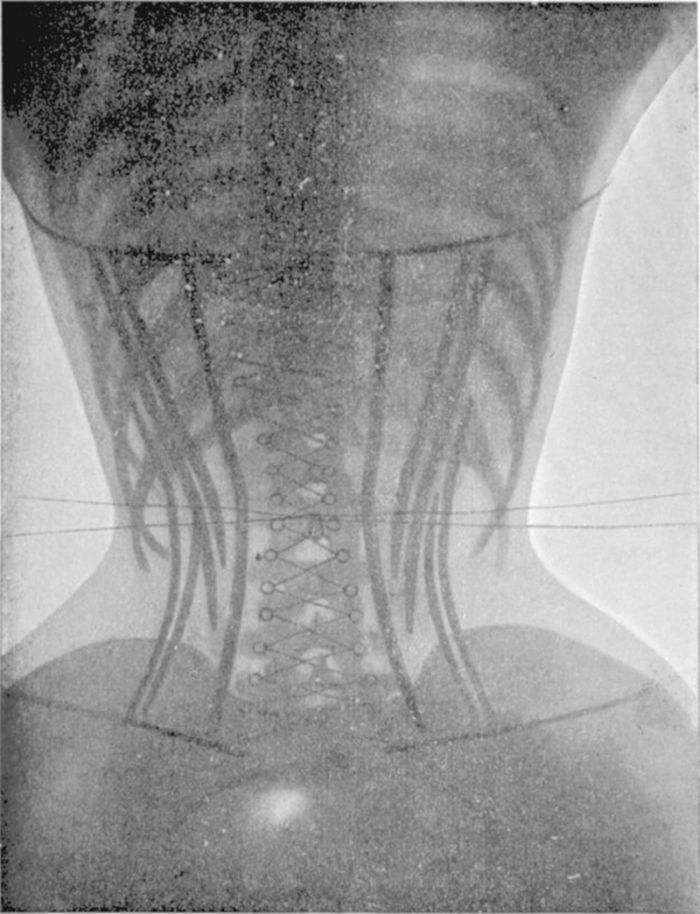

Согласно самой распространенной теории, причиной частых обмороков были корсеты. Слишком тугая шнуровка модных в то время корсетов смещала ребра и сдавливала легкие. Некоторые внутренние органы были буквально придавлены к позвоночнику, в то время как другие – опускались в нижнюю часть живота.

Тугая шнуровка и форма корсета не только не позволяла нормально дышать, но и затрудняла циркуляцию крови в теле. Кроме того, в корсете почти невозможно было есть – еда буквально не помещалась в кишечник.

Подобные деформации иллюстрируются рентгеновскими снимками начала XX века: